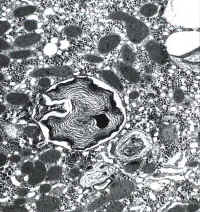

Phospholipidosis: there are foamy hepatocytes plus, under electron microscopy, large lysosomal inclusions composed of densely packed concentric membranes with a fingerprinting pattern. There is also reduction of the crystae in the mithochondria and vesicles in the smooth ER. The lesion was recognized by Oda in Japan in 1969. Later, in 1975, it was recognized by Lullman et al in inborn errors of phospholipid metabolism. Drugs responsible: Colargil (Oda et al. 1969), Amiodarone (Pousell et al.1984).

li-8-4-17.jpg (66449 bytes)

Fig. 8-4-17:

Myelin figures